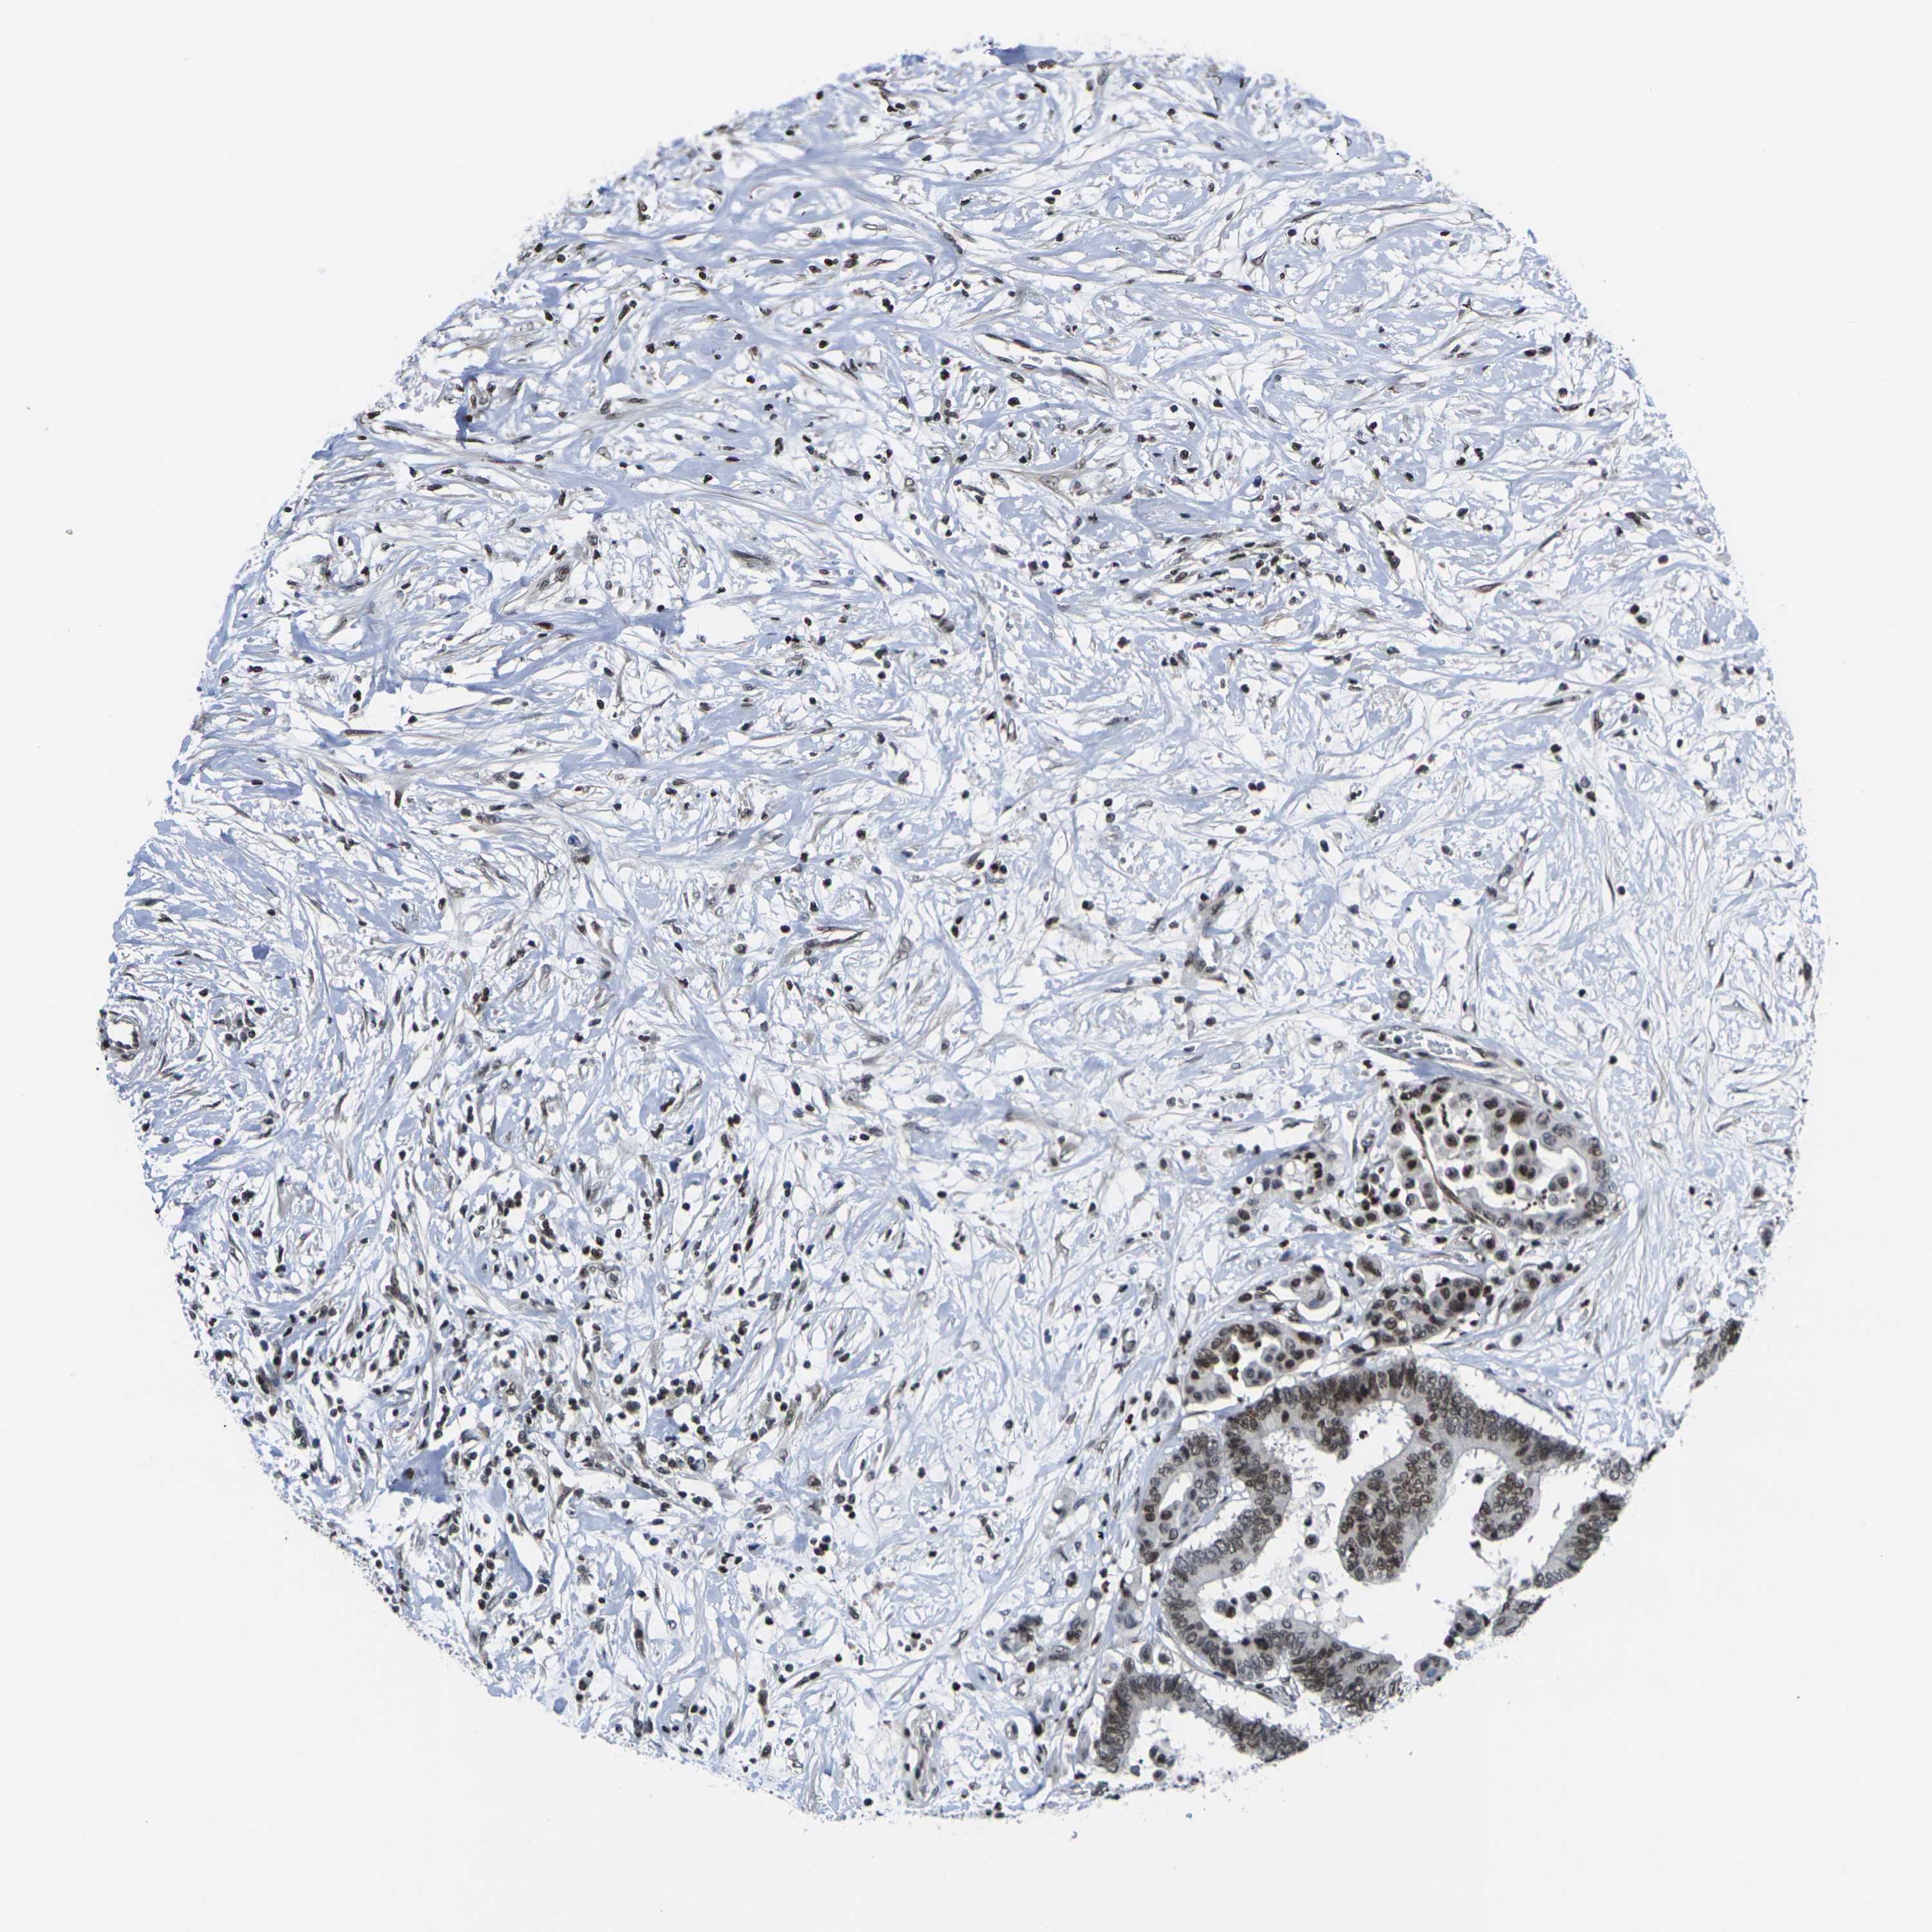

CANCER COLORECTAL CANCER Show tissue menu

Colorectal cancer

Human cancer

Colon adenocarcinoma